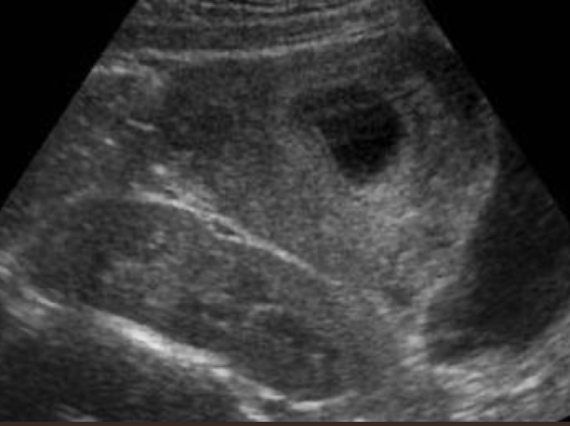

cystic mass

anechoic

smooth, thin, well-defined

round or oval shape

sharpe interference between cyst and renal parenchyma

increased posterior acoustic enhancement

simple renal cyst

MC renal mass lesion

occur in 50% of population

solitary or multiple

s/s: asymptomatic—often incidental finding